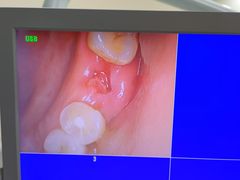

爱贝口腔·牙周诊疗·种植修复中心